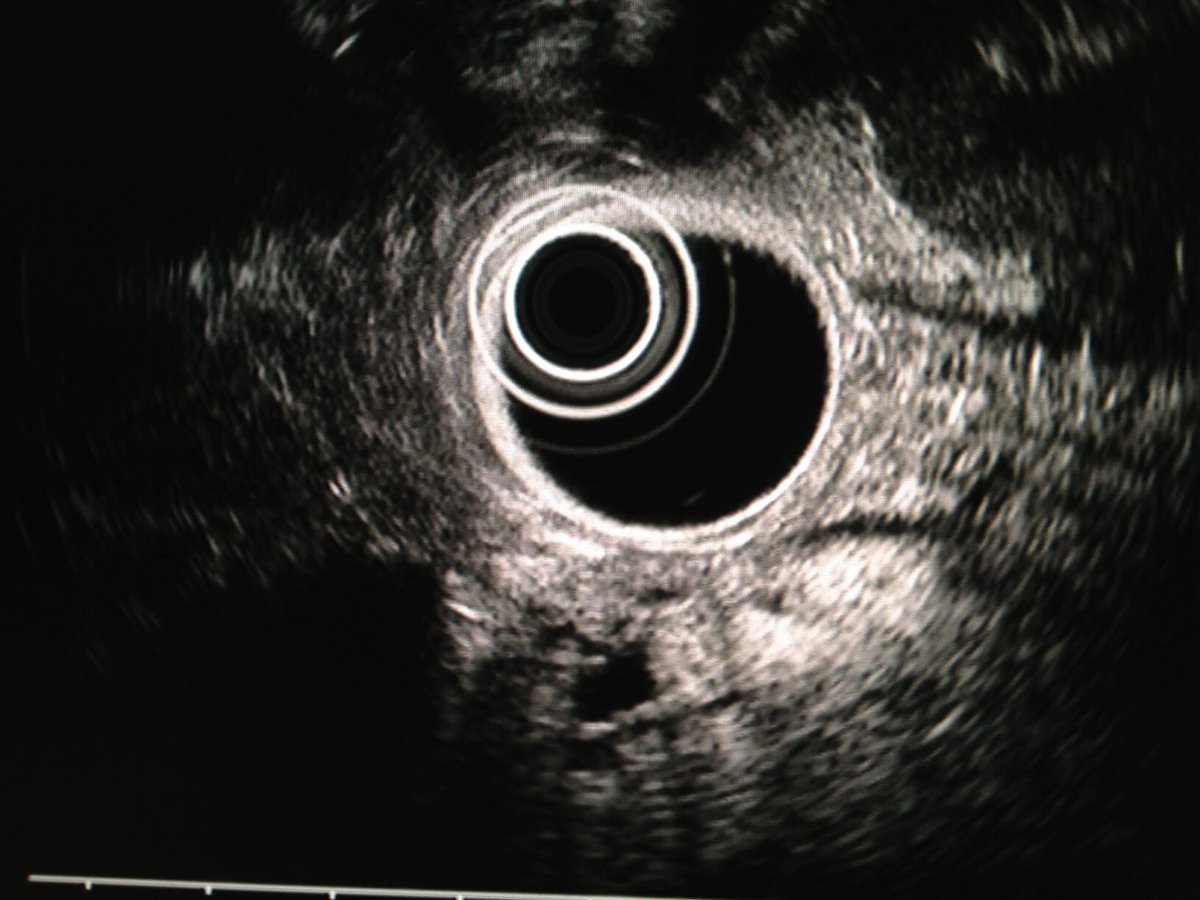

Ampullary cancer

منظار الأشعة الصوتية يظهر انسداد القناة المرارية الرئيسية بورم في فتحة اوددي. أعراض المرض صفار والتهاب في القنوات المرارية في بعض الأحيان. قد يشخص خطئا بحصوة في القناة المرارية إذا لم يتم عمل أشعة النظار الصوتية